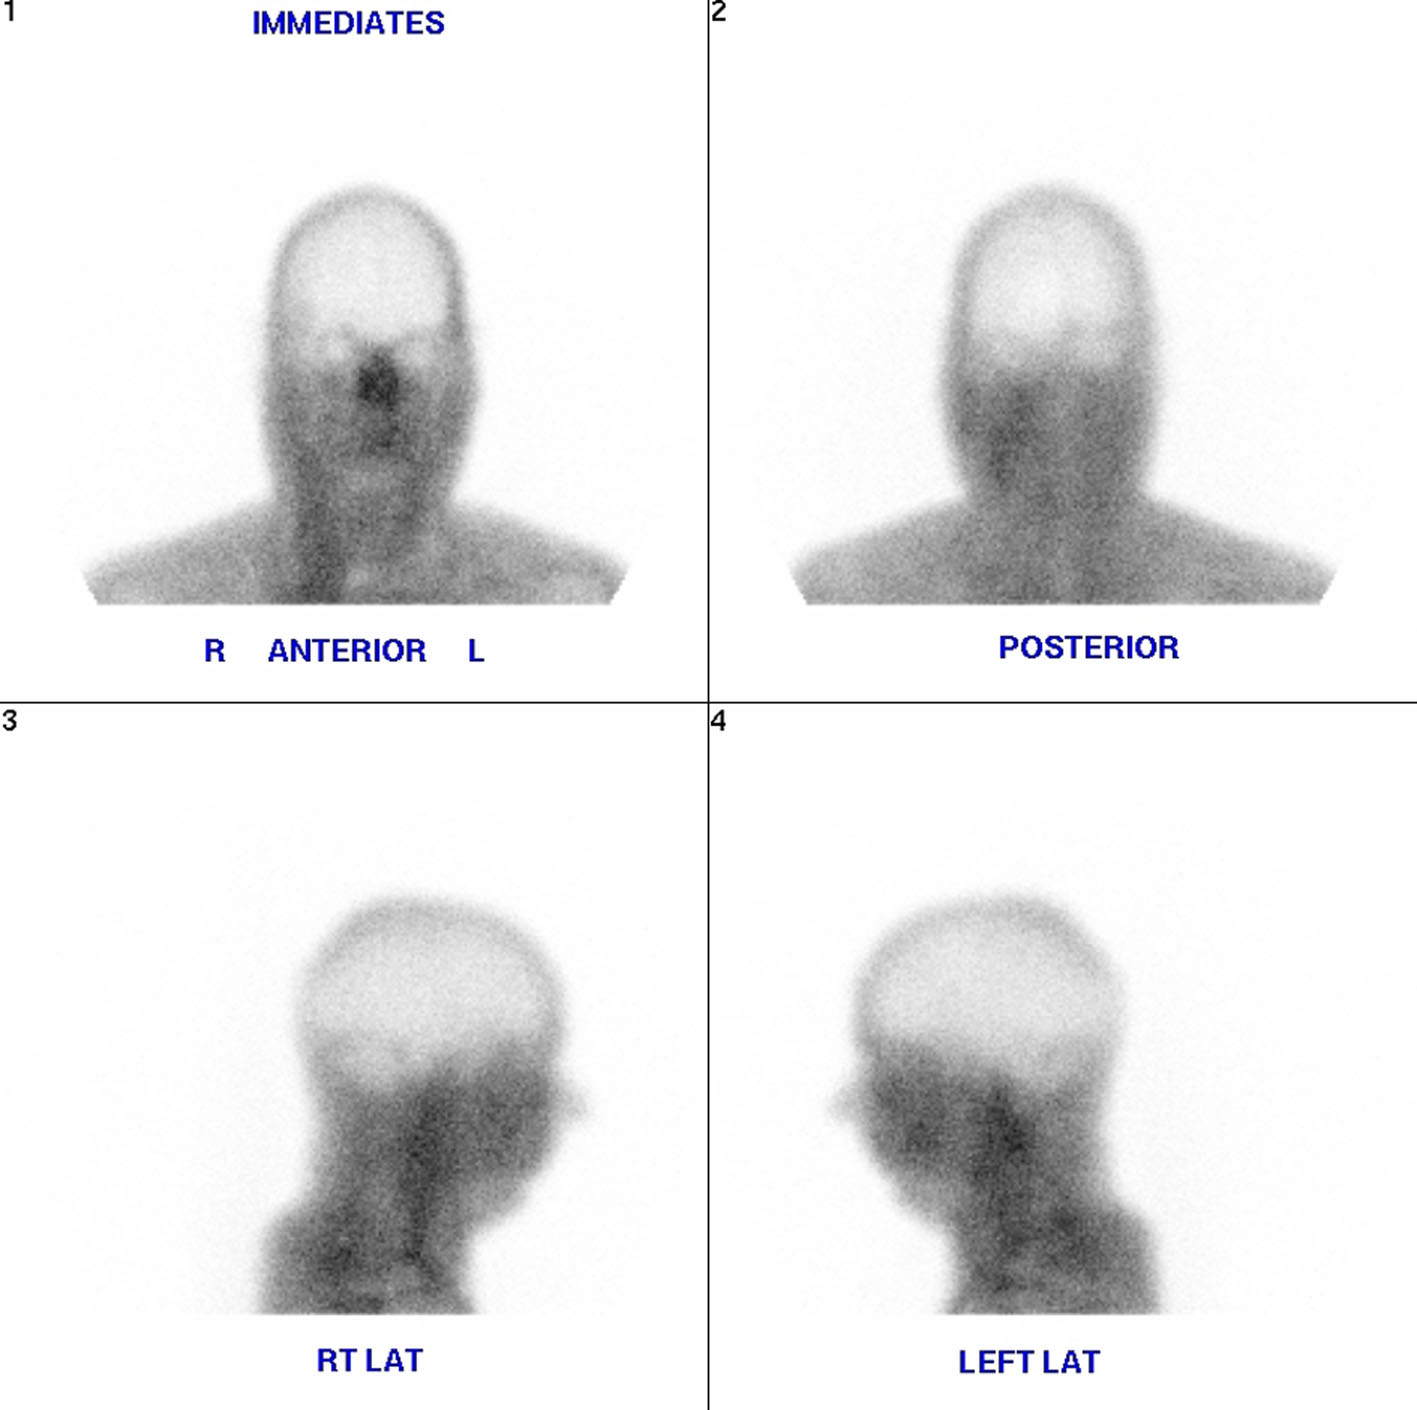

Despite being placed on a sodium bicarbonate drip (150 mEq of 8.4% sodium bicarbonate in 1000 D5W), his metabolic acidosis persisted. He was further given fluid resuscitation of about 3 L, and still remained oliguric. A decision was made by the patient’s nephrologist to start hemodialysis. The sputum culture showed many Streptococcus serogroup C and urine culture showed Klebsiella pnuemoniae ESBL. During a hospital stay of approximately 14 days, the patient received dialysis three times per week. However, his blood urea nitrogen and serum creatinine levels still failed to improve, and he remained in a state of metabolic acidosis. On day 14 of his admission, the patient’s condition deteriorated 2 h in dialysis treatment. He lost his gag and cough reflexes, and his pupils became dilated and fixed. A repeat head CT scan was performed which showed evidence of brain herniation. The brain herniation was confirmed using brain scan flow which showed empty bulb sign (Fig. 3). Repeat lab investigations conducted immediately following hemodialysis revealed a pH of 7.24, HCO3 of 26, sodium of 134 mmol/L, potassium 3.0 mmol/L, urea of 89 mg/dL, and serum creatinine of 11.2 mg/dL. Ultimately, the patient was pronounced brain dead the patient’s family opted for organ donation.

![]() Click for large image | Figure 3. Brain scan flow which showed empty bulb sign. |